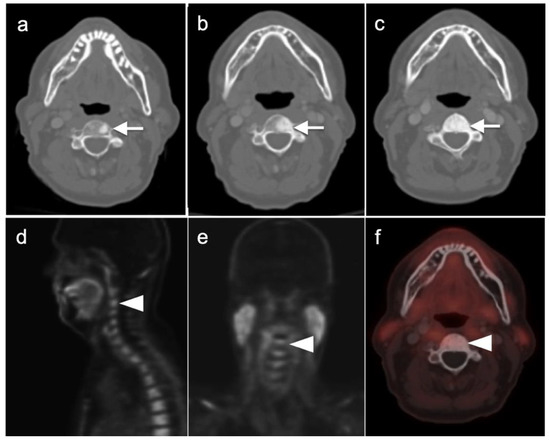

3.2. Urothelial Carcinoma